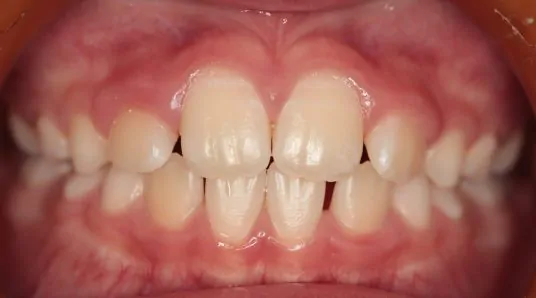

治療前

診断名・主な症状

八重歯・前歯のガタガタ

年齢

11歳女児